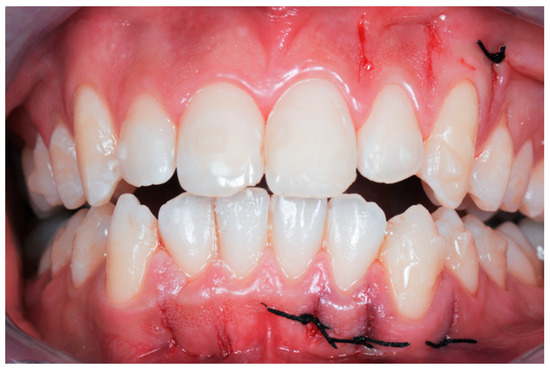

2.3. Surgical Procedure

2.3.2. Example 2—Extraction Space Closure